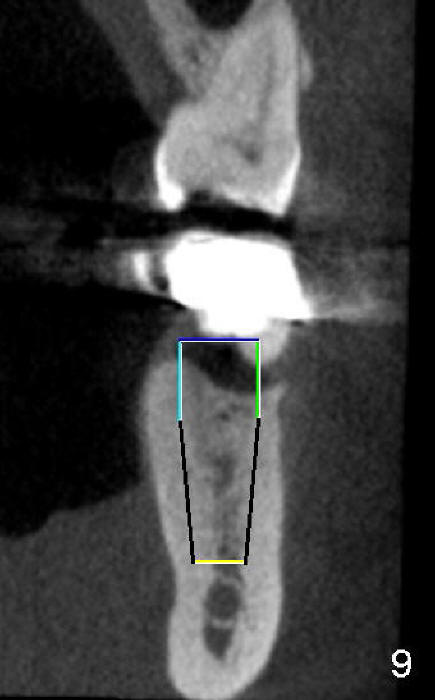

五十多岁的吴先生右下六有根分叉感染(图一),有一次到外地出差疼痛难忍拔除了,一两年后才同意植牙,图二显示已经愈合近远中(M, D)牙槽窝,六乘十七毫米植牙(图三I)好像种得很端正,其实并不完全是这样。让我们回到图二,沿着虚线做个冠状切面,显示右上六号牙以及右下六牙槽骨(图四*),与对侧六号牙冠状切面(图五)对比,右下六牙槽骨往舌侧(L)倾斜(B:颊侧),要植入长而宽的植牙,它就往舌侧倾斜(图八)。为了与对侧牙齿咬合,必须用二十度倾斜的基牙(图六A),但是临床上通过基牙而改变的角度还不够(图七),所以最后牙冠(图十C)不在植牙(I)长轴上,也就是一部分牙冠是悬臂的(*),容易造成陶瓷断裂,基牙松动。避免悬臂牙冠最好的方法便是拔牙后即刻植牙(图九),如果骨质已经吸收,植骨(图十一红色)或者骨扩张时尽量让颊侧骨板往颊侧移动,纠正植牙倾斜角度。